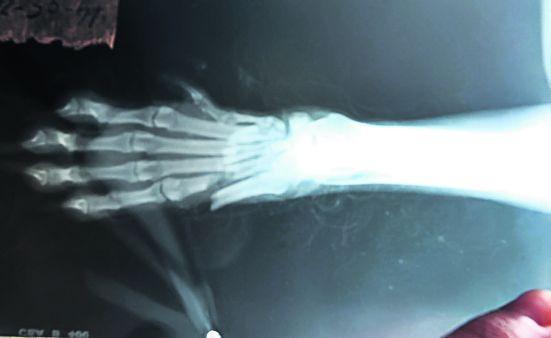

Cum poate să-l muşte pe ditamai bărbatul un asemenea animăluţ? Am fost cu ea la un cabinet veterinar, iar medicii i-au făcut o radiografie şi i-au pus lăbuţa în ghips. Nu am nici o pretenţie, însă nu pot să rămân indiferentă la un gest de o asemenea cruzime. M-am hotărât să vă trimit acest apel pentru a trage un semnal de alarmă cu privire la violenţa faţă de animale.